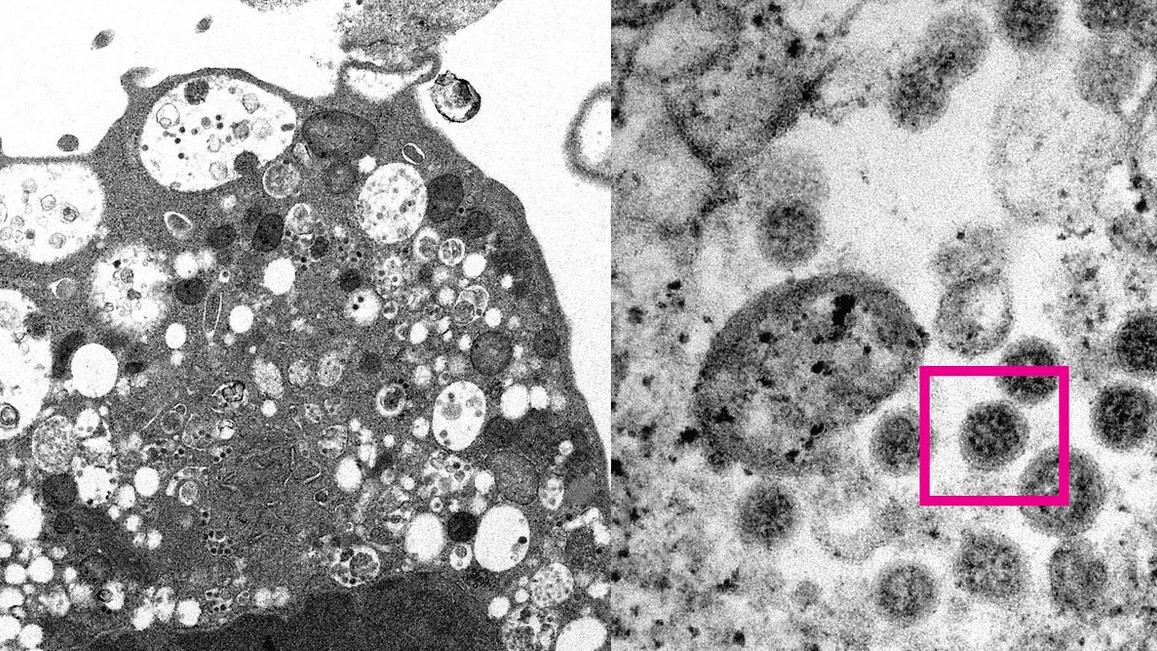

Снимка: med.hku.hk

Университетът на Хонконг публикува снимка на щама на коронавируса омикрон, направена с електронен микроскоп